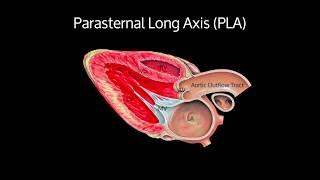

Parasternal Long Axis View - STEP by STEP Point of Care Ultrasound

POCUS 101

33K

109,645

10 лет назад